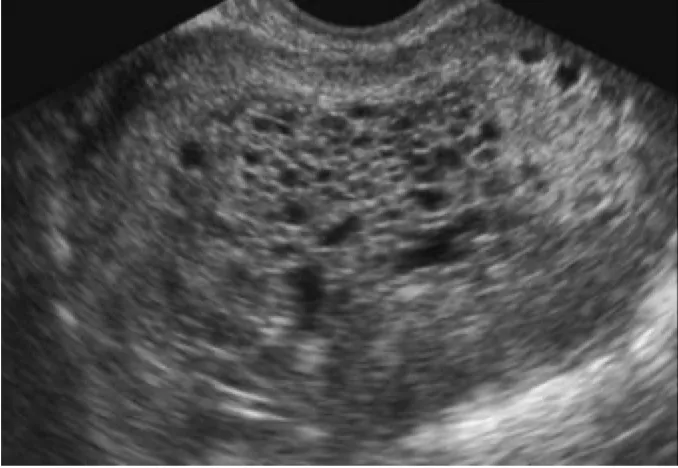

산과력 1-1-0-0인 32세 여성이 불규칙한 질 출혈을 호소하며 병원을 찾았다. 6주 전에 실시한 자궁경부 세포진 검사에서는 이상 소견이 없었다. 골반 초음파 검사 결과를 바탕으로 다음 중 우선적으로 시행해야 할 혈액 검사는 무엇인가?

• 초음파 상 눈보라 현상(snowstorm pattern)이 관찰되어 포상기태가 의심된다.

• 포상기태 진단 및 기타 감별진단을 위한 호르몬 검사는 hCG이다.